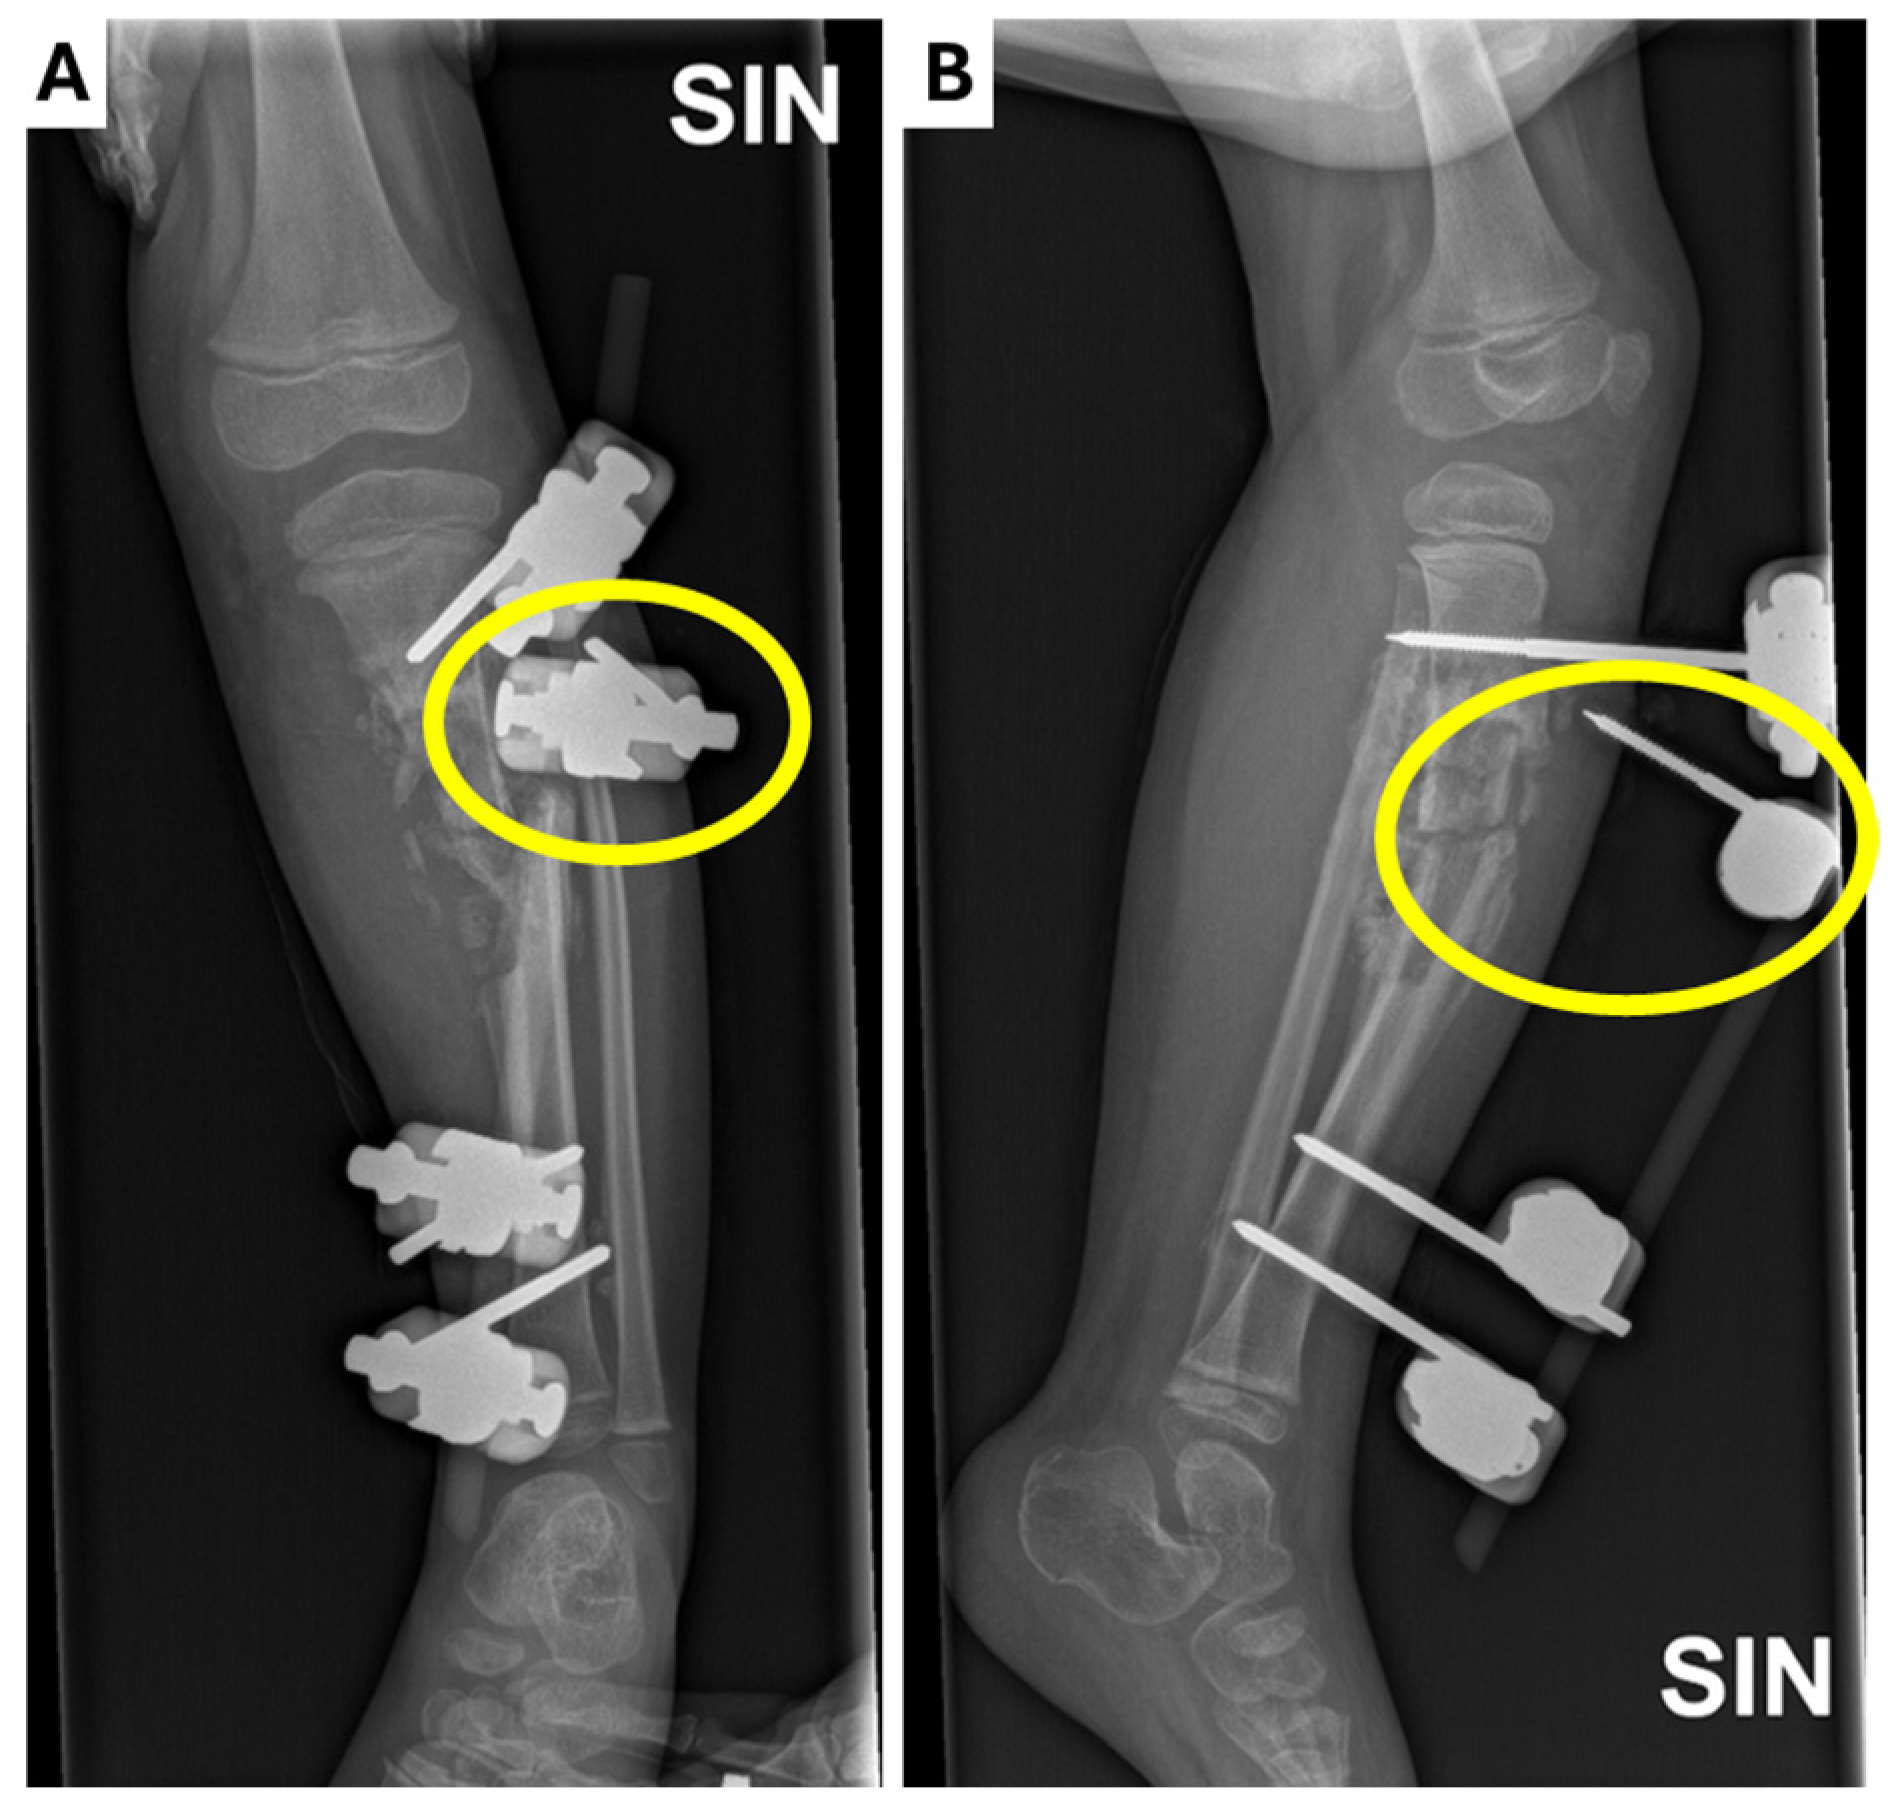

Figure 3.

Radiological examinations of the left leg showing the dislocation of one of the external fixators (yellow circle) in the (A) X-ray anterior–posterior projection; (B) X-ray lateral projection.